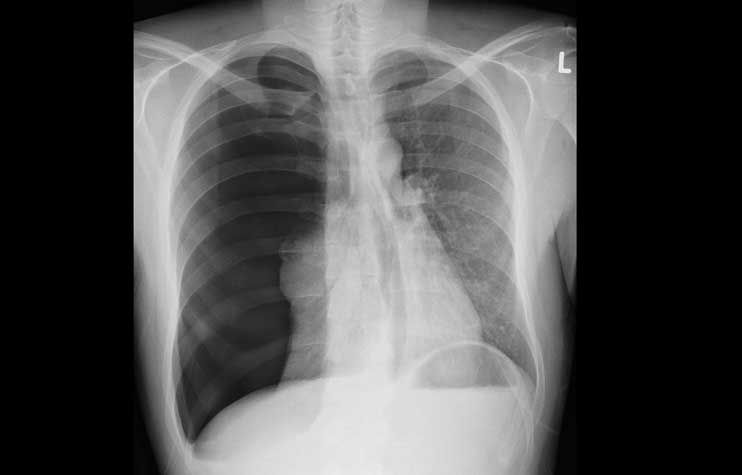

Röntgen-Thorax

Der konvetionelle Röntgen-Thorax hat sich im Laufe der Zeit zu einem unverzichtbaren zentralen Bestandteil in der Diagnostik sowie zur Beurteilung des Therapieverlaufes zahlreicher Herz- und Lungenerkrankungen entwickelt. Des Weiteren spielt er eine wichtige Rolle in der Beurteilung der Narkose- und Untersuchungsfähigkeit eines Patienten. Nicht selten liefert er relevante Nebendiagnosen der Lunge oder des Skelettes (Tumoren, asbestinduzierte Lungenveränderungen, Wirbelkörper- oder Rippenbrüche, Schilddrüsenerkrankungen etc.).

Darstellung von Erkrankungen im Röntgen-Thorax:

Kardiale Dekompensationsstauung

Die Vorteile des Röntgen-Thorax liegen in der schnellen Verfügbarkeit zu allen Tages-, und Nachtzeiten ohne spezielle Vorbereitung des Patienten. So können Erkrankung wie beispielsweise eine Lungenentzündung oder eine kardiopulmonale Kreislaufentgleisung gut erkannt und rechtzeitig therapiert werden. Aber auch akut lebensbedrohliche Erkrankungen wie der Spannungspneumothorax können sicher ausgeschlossen werden.

Selbst bei bettlägerigen Patienten ist ein Röntgen-Thorax im Liegen mit guter Aussagekraft durchführbar.

Die Lage von eingebrachten Fremdkörpern (zentralen Kathetern, Herzschrittmacher sowie Defibrillator, Magensonde, Herzklappen, Trachealtubus etc.) kann, wie auch versehentlich verschluckte oder durch Unfall inkorporierte Fremdkörper grundsätzlich gut beurteilt werden.

Darüber hinaus hat der Röntgen-Thorax den Vorteil einer sehr niedrigen Strahlendosis (im Schnitt um den Faktor 300 niedriger als im vergleichbaren Thorax- CT).

Selten und erst bei schwierigen Bildkonstellationen oder fehlender Übereinstimmung mit den Beschwerden des Patienten ist eine weiterführende Abklärung mittels aussagekräftigerer aber strahlungsintensiverer Computertomographie (CT) nötig.